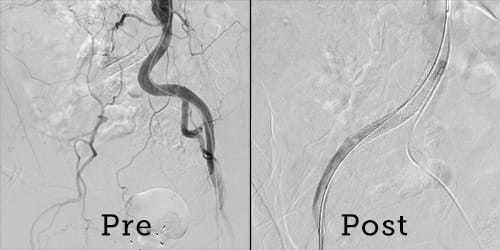

As with a cardiac catheterization, Dr. Shishehbor used wires, medicated balloons and stents to clear and clean his patient’s vessels and stent them to prevent them from closing again. He entered Daniel’s leg from the foot and the groin, to suck out clots and clean up the arteries. Some blockages can be a foot or more in length, Dr. Shishehbor said.

“Every artery in his right leg was blocked 100 percent from his belly button to his ankle,” Dr. Shishehbor said. “He ended up losing nothing, and now he’s walking and doing his squats. He’s a miracle man. It’s unbelievable.”